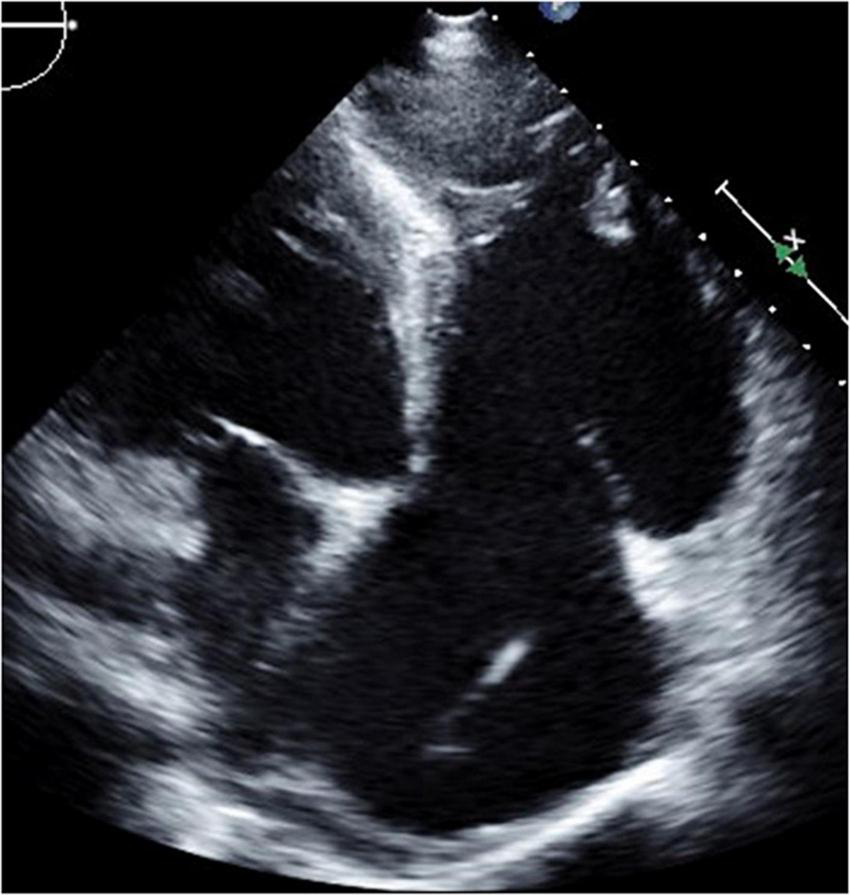

FIGURE 7

Short-axis view at end-diastolic phase of transthoracic echocardiography in Case 4.

FIGURE 8

Four-chamber view at end-systolic phase of transthoracic echocardiography in Case 4. Note that the tricuspid valve does not close at all, and the right atrium is hugely dilated.